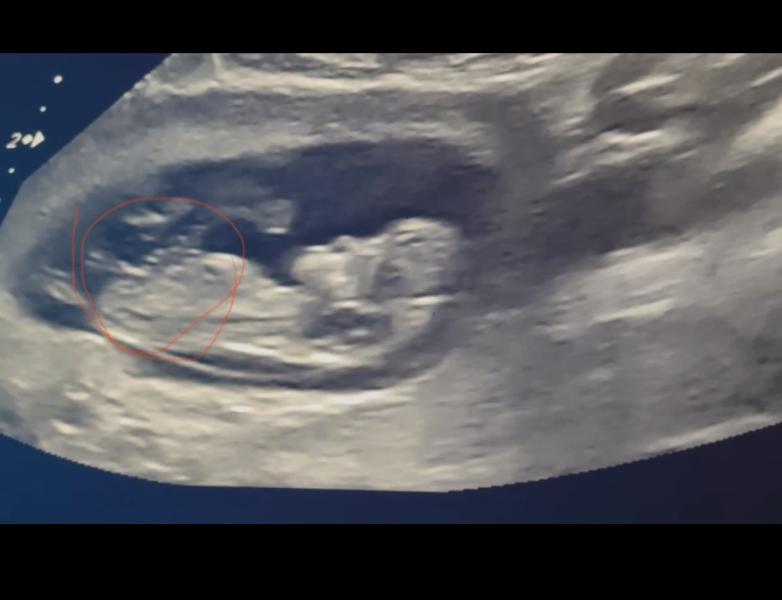

девочки, кто это?😂

Пока похоже на девочку, но по половому бугорку для определения срок должен быть от 12 недель)

Девочка по половому бугорку.

Но рано ещё , этому методу не особо надо доверять. Если было бы всё так просто то сразу бы на 1 скрининге и писали пол в заключении.

У вас девочка по бугорку